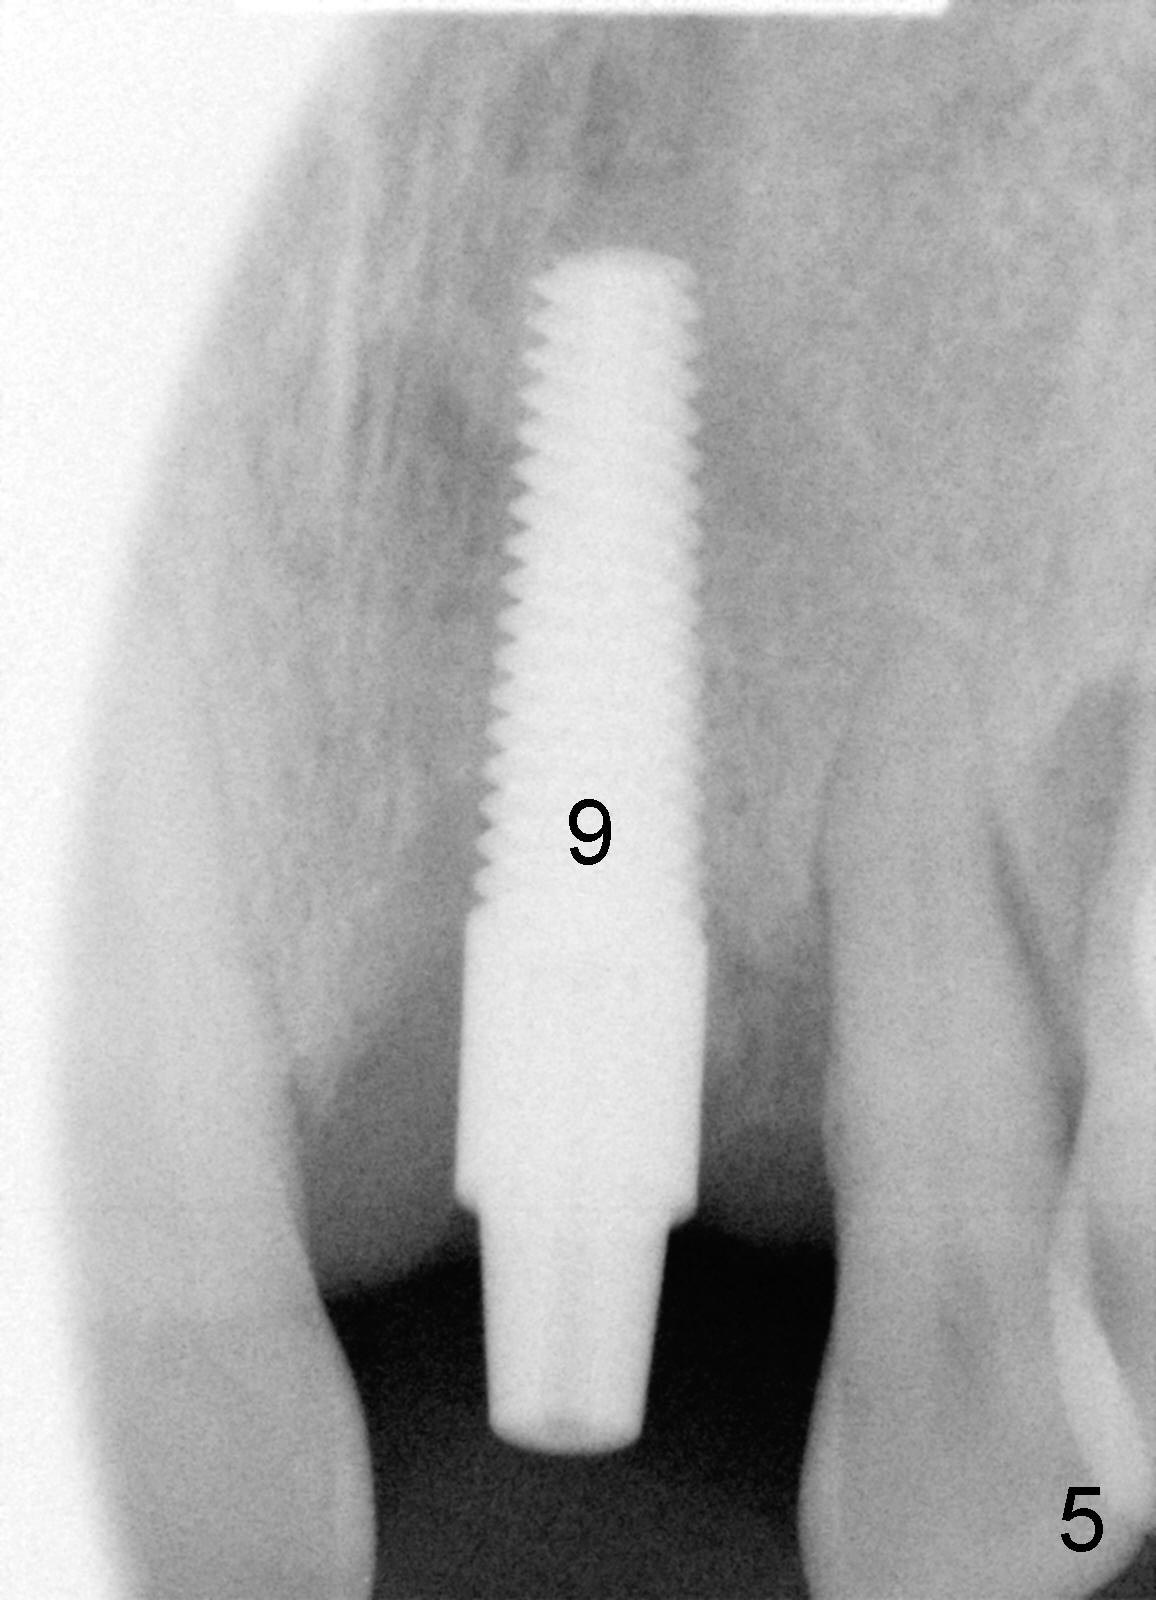

The most severely affected teeth (#6,7 and 9) are extracted and immediately replaced by 4x20 mm (#7) and 5x20 (#6,9) implants (Fig.4,5). Straight (0 degree) uniposts (3 and 4 mm, respectively) are rotated tightly into the wells of the implants by hand screw driver. In order to have reversibility to hybrid denture in the future, these uniposts are not cemented. Heavy retention grooves are placed between the uniposts and implants. Provisionals are fabricated immediately and cemented temporarily. To increase stability, flowable composite is added to the area between the provisionals of #6 and 7.

The provisional of #9 is still wiggling a little bit buccolingually. It is probably due to loose connection between the implant and the abutment, although follow up PAs do not support it (Fig.7,8; ^: bone graft at the time of immediate implants).